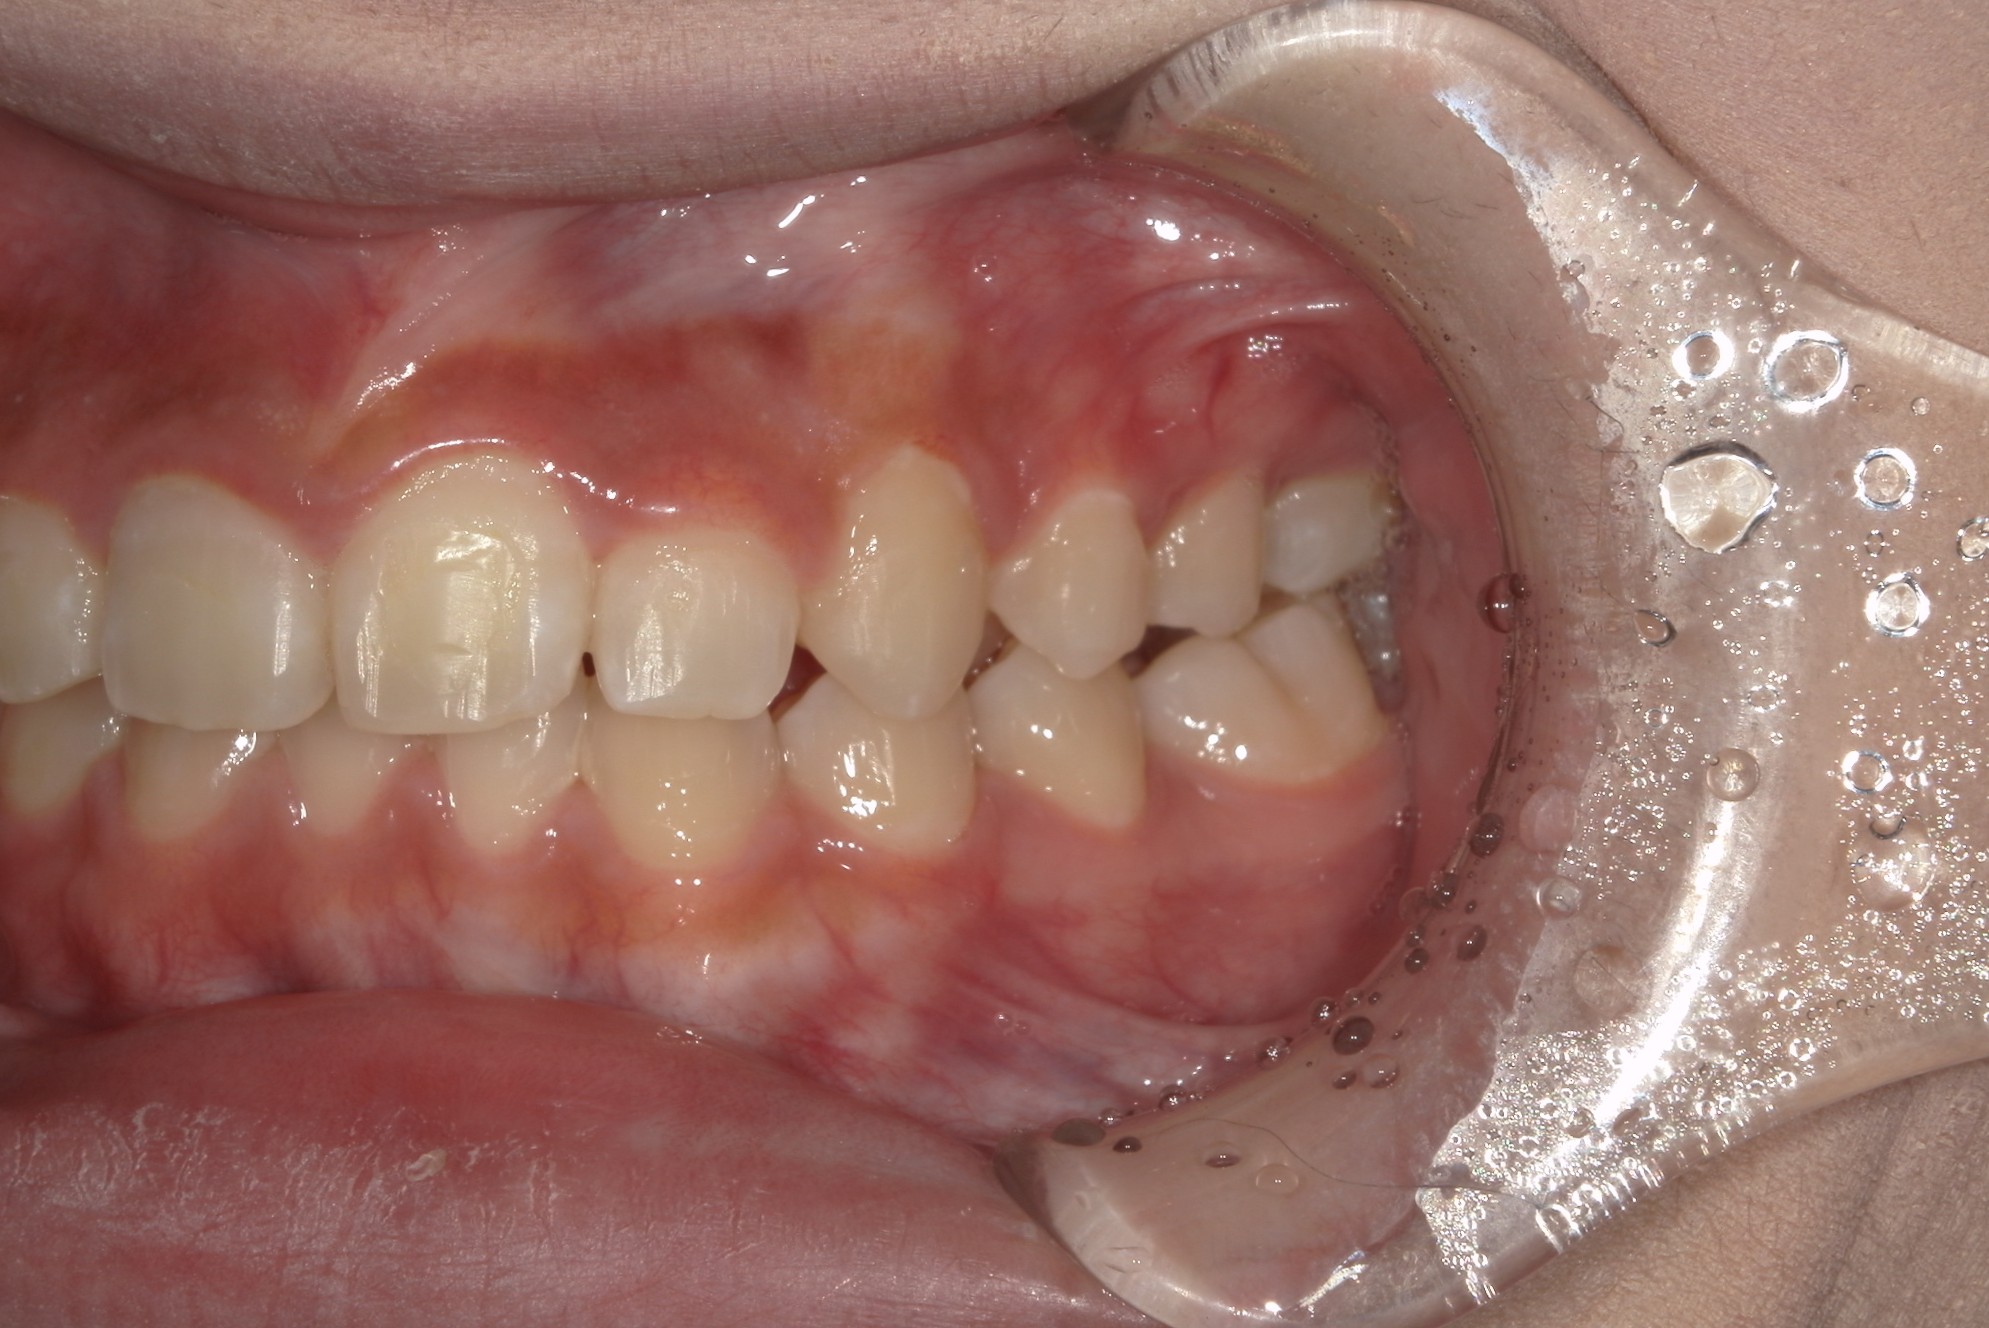

矯正術前:右側

矯正術後:右側